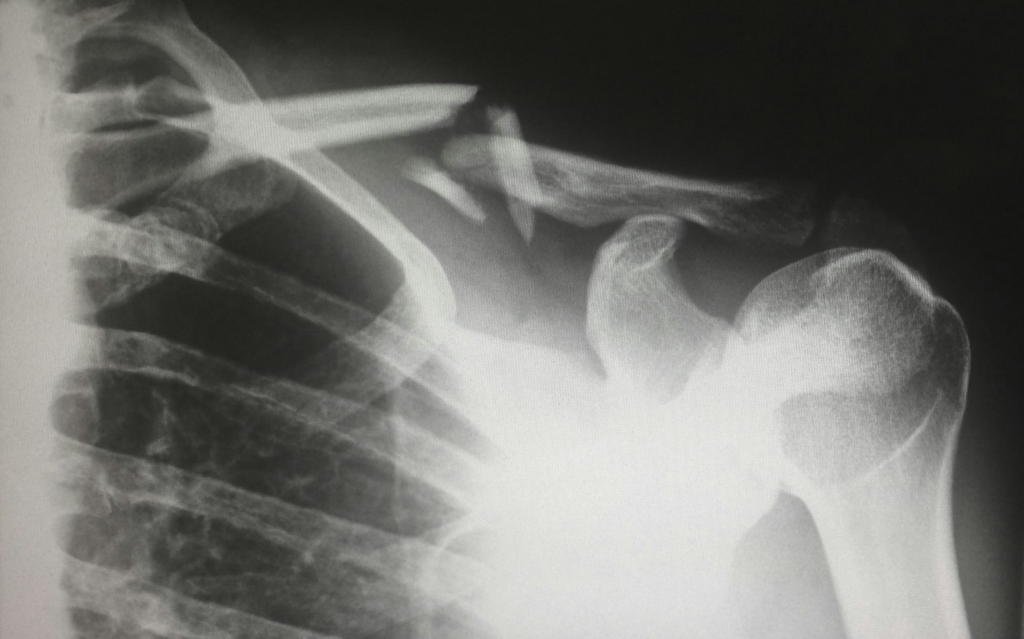

A serious injury can disrupt your life in ways you don’t fully realize at first. Broken bones and neck injuries […]